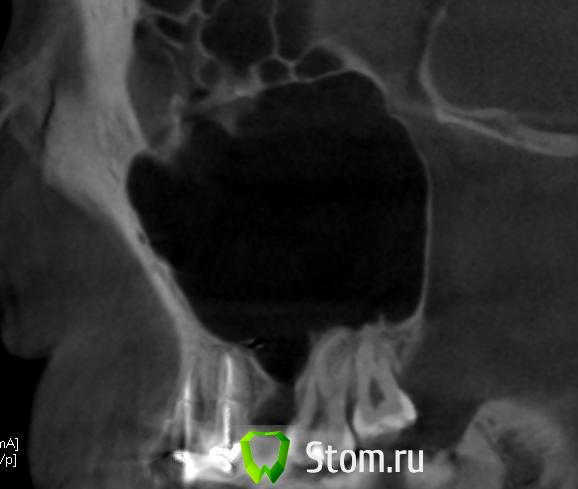

doktorenok Опубликовано 5 декабря, 2011 Поделиться Опубликовано 5 декабря, 2011 Вот чисто теоретически Возможна ли здесь имплантация? Если да, то какова последовательность действий по пластике? Зуб удален год назад, соустье ушито, жалоб никаких не было. Ссылка на комментарий

Bier Опубликовано 5 декабря, 2011 Поделиться Опубликовано 5 декабря, 2011 на первом этапе 3д пластика + синус, потом имплантация. Ссылка на комментарий

doktorenok Опубликовано 5 декабря, 2011 Автор Поделиться Опубликовано 5 декабря, 2011 на первом этапе 3д пластика + синус, потом имплантация.Т.е.:окно-отслаиваем мембранув месте соустья-скальпелемв лунку и под мембрану пазухи смесь ауто+био-оссщечно винтами кортикалку от блокасверху мембрана. Так? Ссылка на комментарий

Bier Опубликовано 6 декабря, 2011 Поделиться Опубликовано 6 декабря, 2011 одно но, Кюри признает только аутокость.Мембрана не очень нужна, роль мембраны и каркаса выполняет "фанера" из кортикальной пластинки. Лучше все это перекрыть VIP-CT лоскутом по Скляру. Ссылка на комментарий